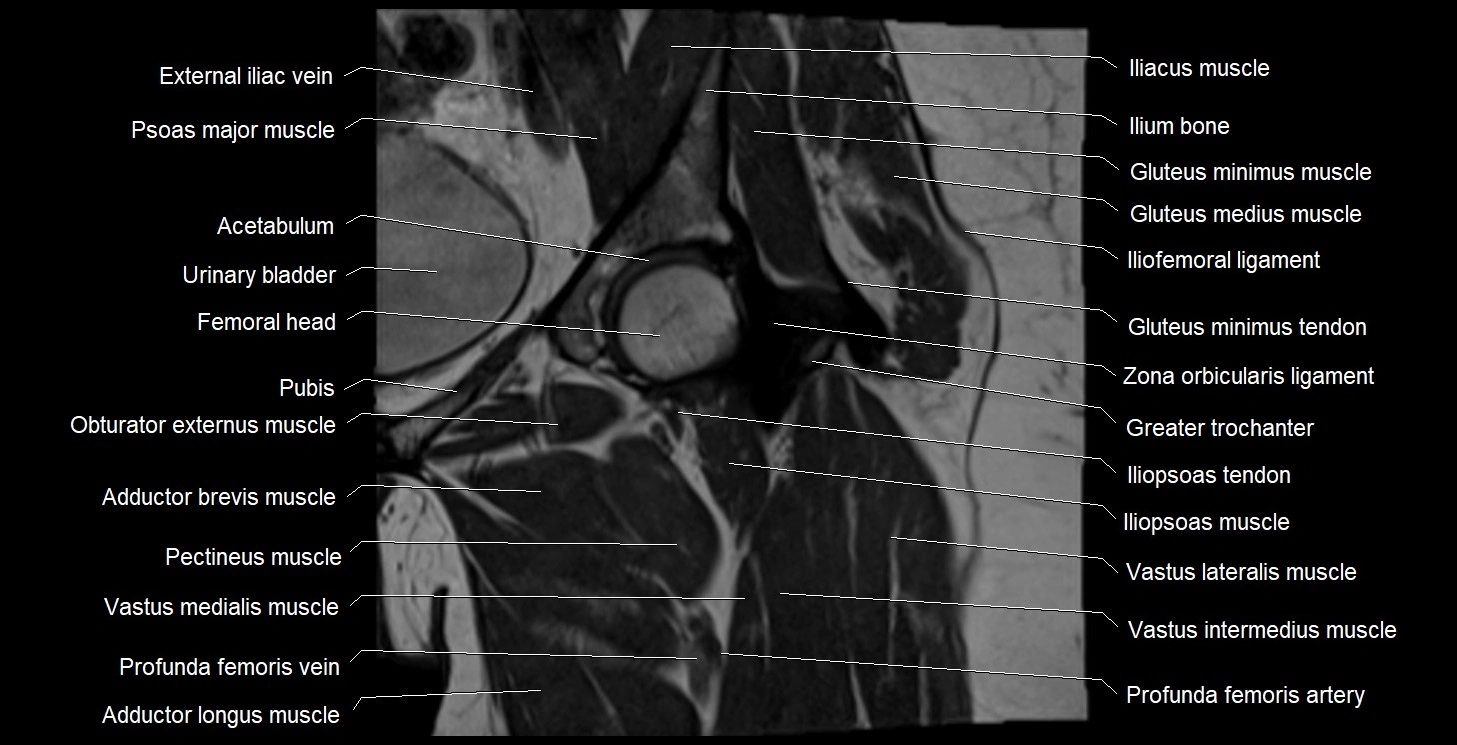

- Acetabulum

- Deep femoral vein (profunda femoris vein)

- Gluteus medius muscle

- Gluteus minimus muscle

- Gluteus minimus tendon

- Greater trochanter

- Head of femur

- Iliofemoral ligament

- Iliopsoas muscle

- Iliopsoas tendon

- Ilium bone

- Obturator externus muscle

- Pectineus muscle

- Psoas major muscle

- Pubic bone

- Urinary bladder

- Vastus intermedius muscle

- Vastus lateralis muscle

- Vastus medialis muscle

- Zona orbicularis ligament